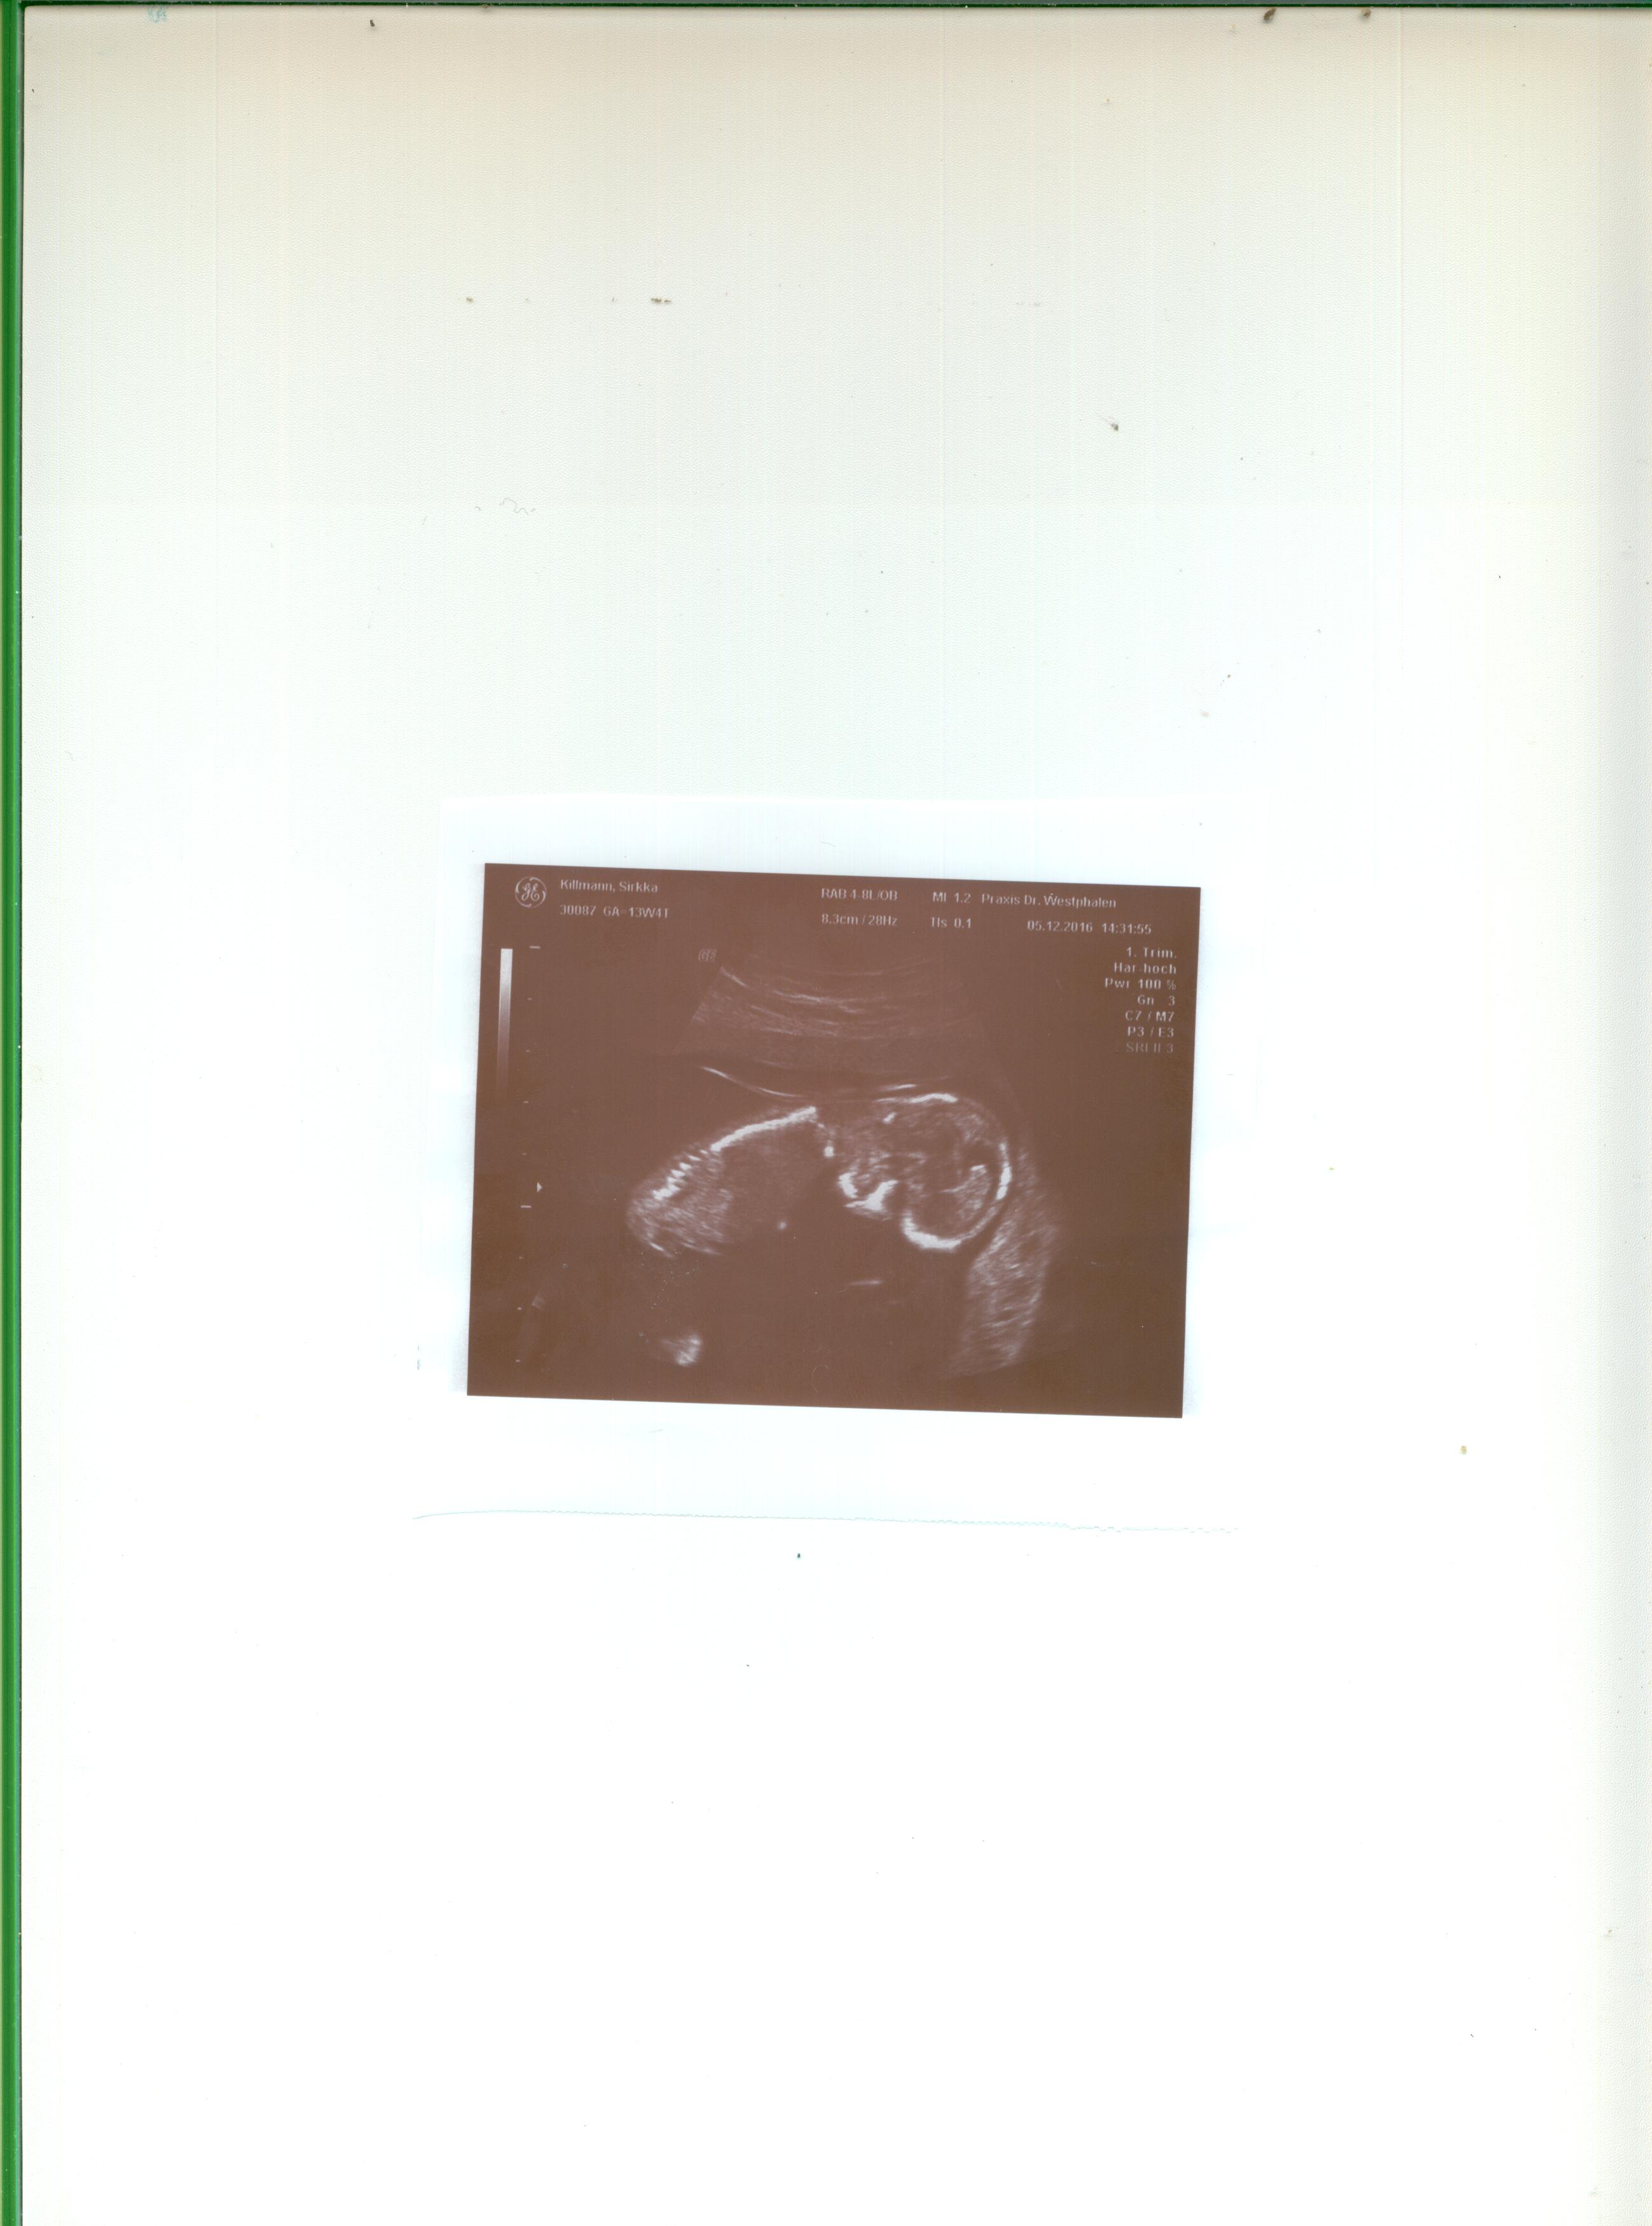

I just had my 13 weeks and four day scan Today and am so curious what gender it may be. As for the nub, I am not even sure if I can see it in this ultrasound. I would be so grateful if you could help me out if you can see a nub, and if yes, does it look boy or girl to you? The image might be a little small, but I have no clue how to make it bigger.

Attachment 33986